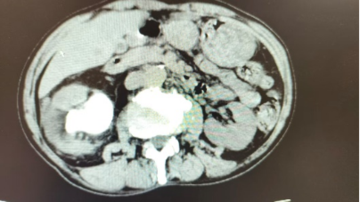

体检意外发现: 沉默的“石头危机” 李先生(化名)50余岁,在一次常规体检中被告知“右肾结石”。他没有腰痛、血尿,也无发热等不适,原以为只是“小问题”。在西安医学院第一附属医院泌尿外科门诊,副主任医师宋益挺详细了解病史、结合影像资料后,建议完善泌尿系CT检查。然而,检查结果却让人意外:右肾重度积水,肾盂系统内充满铸型结石,最大直径约6cm。 这是典型的肾铸型结石(Staghorn